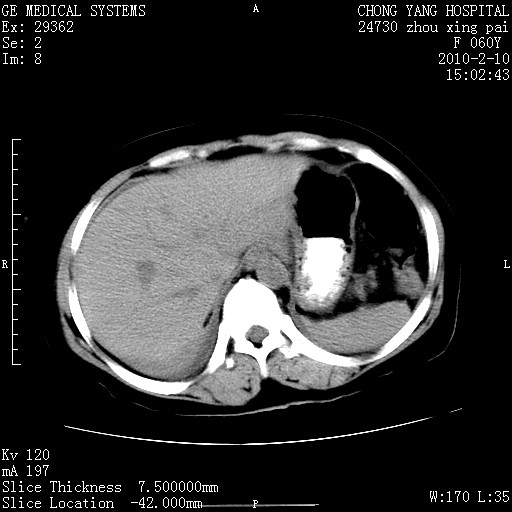

标题: CT24682:F60Y 腹痛 其它不详 [打印本页]

标题: CT24682:F60Y 腹痛 其它不详

胆总管末端梗阻!结石?肿瘤?建议增强!必要时行ercp!

胆总管末端梗阻!结石?胰腺影增粗,以胰腺头部为著,胰周看见渗出影,双侧胸腔积液,(胸膜反应)考虑胰腺炎。

1)胆总管末端梗阻,不排除结石所致可能。2)胰腺炎。3)慢性胆囊炎可能。4)左侧输尿管上段扩张。5)少量腹水。6)双侧少量胸腔积液,伴两下肺部分肺萎陷。

1)胆囊炎。2)胆源性胰腺炎。3)右肾周筋膜增厚,肾旁前间隙积液。4)左侧输尿管上段扩张。5)少量腹水。6)双侧少量胸腔积液,伴两下肺部分肺膨胀不全。

急性胰腺炎所致胆总管扩张!